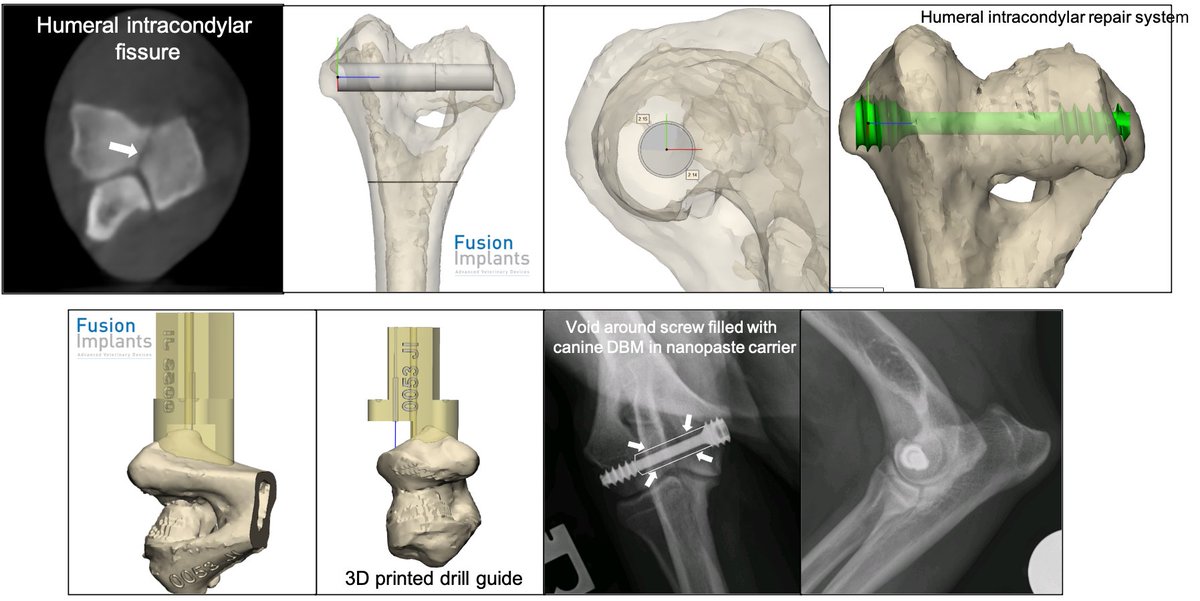

3D-printed drill guide from @FusionImplants making placing HIRS screw for canine humeral intracondylar fissure super-easy and predictable #progress @ESS_Health

First there was one; now there are three. Beautiful titanium alloy headless, self-compressing screws for humeral intracondylar fissure repair in dogs as part of the Humeral Intracondylar Repair System @FusionImplants @veterinarytbank @m_ben_w @bdxlascelles @vosdvm

Pop over to Insta to meet Ollie, who travelled a few hundred miles to benefit from custom drilling guides, the HIRS from @FusionImplants and a good bit of experience…instagram.com/p/CXeXpOpICPY/…

Check out this recent case from @ColinDriver1 using @FusionImplants custom 3D printed drill guides